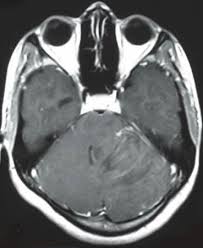

Computed tomography ct scan revealed symmetrical ventricular dilatation. Ported as a very common cause of shunt dysfunction 5 5. After placement of vp shunt the air introduced to the brain and the patient developed tension pneumocephalus which is neurosurgical emergency.

3 the purpose of ventriculoperitoneal shunt vps surgery is to allow csf flow through a shunting mechanism from the intracranial ventricles to the peritoneum. Ct brain revealed pneumoventricle and extensive subdural pneumocephalus overlying bilateral frontal lobes causing compression of the frontal lobes and separation of their tips characteristic of the mount fuji sign fig. In 126 frontal approach 48 malfunction and obstruction with shunt revi sion were seen.